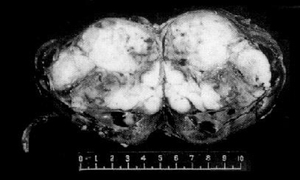

肾癌翻花,中医病名。是指以阴茎龟头出现丘疹、结节状坚硬物等,溃后如翻花状,有特异恶臭和脓性分泌物为主要表现,发生于阴茎的癌病类疾病。本病多见于中老年人,但青壮年亦有发病。相当于西医阴茎癌。

2、开始在阴茎头局部出现硬块或红斑,突起小肿物或经久不愈的溃疡,由于包皮掩盖未引起足够重视,以后有血性分泌物自包皮口流出,肿瘤可突出包皮口或穿破包皮呈菜花样,表面糜烂,渗出物恶臭,多不妨碍排尿。晚期癌肿可侵及阴茎的全部、耻骨部及阴囊,局部失去正常形态而在耻骨部形成一巨大的癌性溃疡。